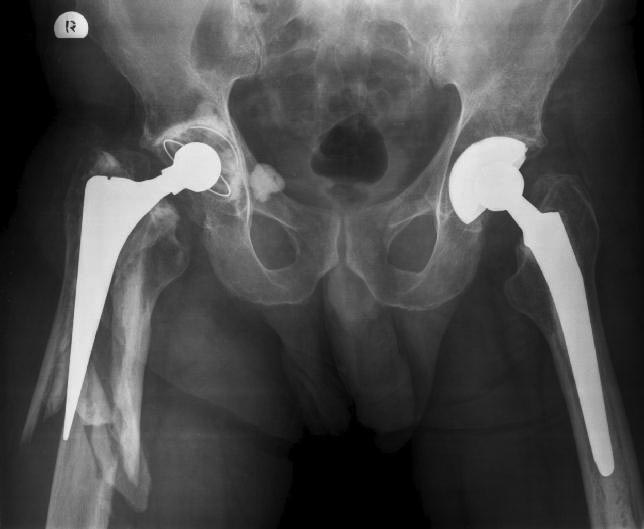

[Ortho] Перипротезный перелом

Снимки.